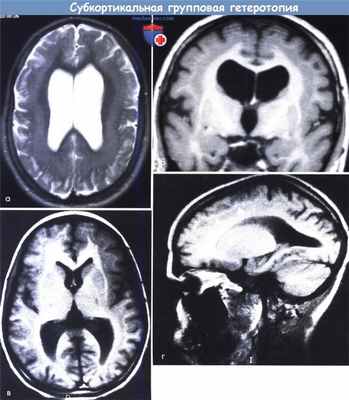

Субкортикальная групповая гетеротопия («двойная кора»):

(а) Аксиальный срез МРТ: широкие, непрерывные группы с таким же сигналом как от коры.

(б) Коронарный срез: в этом же случае имеется расширение желудочков преимущественно спереди.

(в, г) MPT, Т1-взвешенная последовательность — (в) аксиальный срез, (г) сагиттальный срез -тонкий слой белого вещества, лежащий между истинной корой и тонкой линейной гетеротопией серого вещества (стрелки).